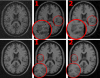

This is a fast and robust implementation of the popular Nonlocal Means for MRI-Rician denoising. It works by computing the non-local weights based on distances in a features space comprising the local mean value and gradients of the image.

It can reach an acceleration factor of 20x over the original implementation, with an improved performance for medium-low SNR images.